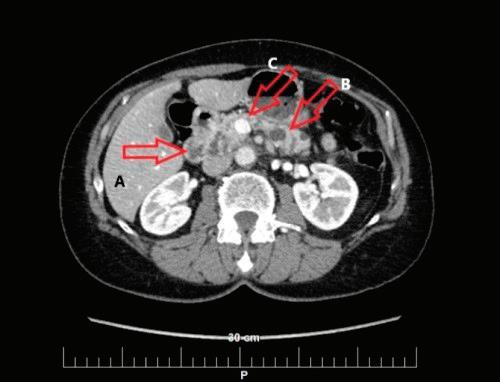

48 КИСТИ НА ПАНКРЕАСАЗНАЧЕНИЕ, ДИАГНОСТИЧНИ ДИЛЕМИ И ИНДИКАЦИИ ЗА ХИРУРГИЯ Н. Шумка, П. Карагьозов

2023 БРОЙ 74 03.2020 СПЕЦИАЛИЗИРАНО ИЗДАНИЕ ЗА ЛЕКАРИ WWW.MEDMAG.BG БРОЙ 74 03.2020 БРОНХОДИЛАТАТОРИТЕ С ДЪЛГО ДЕЙСТВИЕ ПРИ ЛЕЧЕНИЕ НА СТАБИЛНА ХОББ СТР. 4 ХРОНИЧЕН РИНОСИНУИТ С НАЗАЛНА ПОЛИПОЗА И ЕОЗИНОФИЛНО ВЪЗПАЛЕНИЕ СТР. 24 КИСТИЧНИ ПАНКРЕАСНИ НЕОПЛАЗМИ СТР. 62

Доц. д-р Цветелина Тотомирова